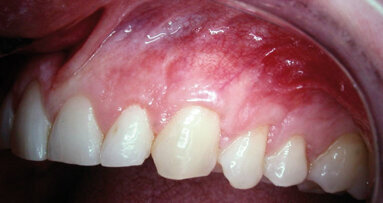

The existence and preservation of attached keratinized gingiva around natural teeth and dental implants plays an important role in periodontal[1] and peri-implant health.[46,47] This article describes a novel surgical technique that addresses multiple adjacent Miller Class II and III recession defects[5] in a predictable one-staged surgical procedure. The goals of treatment are to improve esthetic outcomes and gain clinical attachment and keratinized tissue levels in addition to possible root coverage.

A combination of traditional periodontal plastic procedures is used, following sound, evidence-based techniques. To date, more than 100 surgical cases have been completed. Surgical steps and rationale for this new technique are detailed here, and representative cases are shown (Figs. 1–12).

As many epidemiological reports suggest, gingival recession affects the majority of the adult population.[2,3] Gingival recession is defined as the apical migration of the soft-tissue margin around teeth leading to exposure of the cementoenamel junction (CEJ) and the dentinal root surface4 and is classically categorized by Miller.[5,6] The philosophy for increasing the zone of keratinized tissue for teeth is for attachment stability, facilitation of plaque control and to prevent further gingival recession from frenal/muscle pulls.[6,7]

Recession in multiple adjacent teeth can occur for a variety of reasons: the patient’s iatrogenic habits; history and/or treatment of chronic periodontal disease by traditional flap therapy; anatomy/malpositioned teeth in the alveolar ridge corridor compromising attachment apparatus; muscle/frenal attachment levels at or beyond the mucogingival junction (MGJ); secondary parafunctional habits; and the obvious long-standing results of a history of chronic untreated periodontal disease.

Patients chosen exhibit posterior sextants of recession with interproximal bone loss (Miller II or III) and encroachment of gingival recession on the MGJ, commonly with frenal pulls and muscle attachments, which may or may not have played a role in the etiology of attachment loss but will play a role on the success and stability of surgical treatment to resolve progressive recession.[15,49]